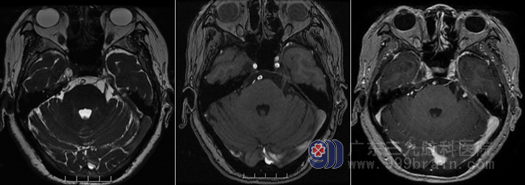

神经外十科对三叉神经痛的治疗确实有独到之处,微创穿刺球囊压迫和显微镜下微血管减压术均在国内属一流水平。李阿姨入院后,医生团队立马给完善了整套的检验和检查,头颅MR检查显示:头颅MR检查显示:右侧三叉神经、面听神经各有血管压迫,目前诊断考虑三叉神经痛合并面肌痉挛。